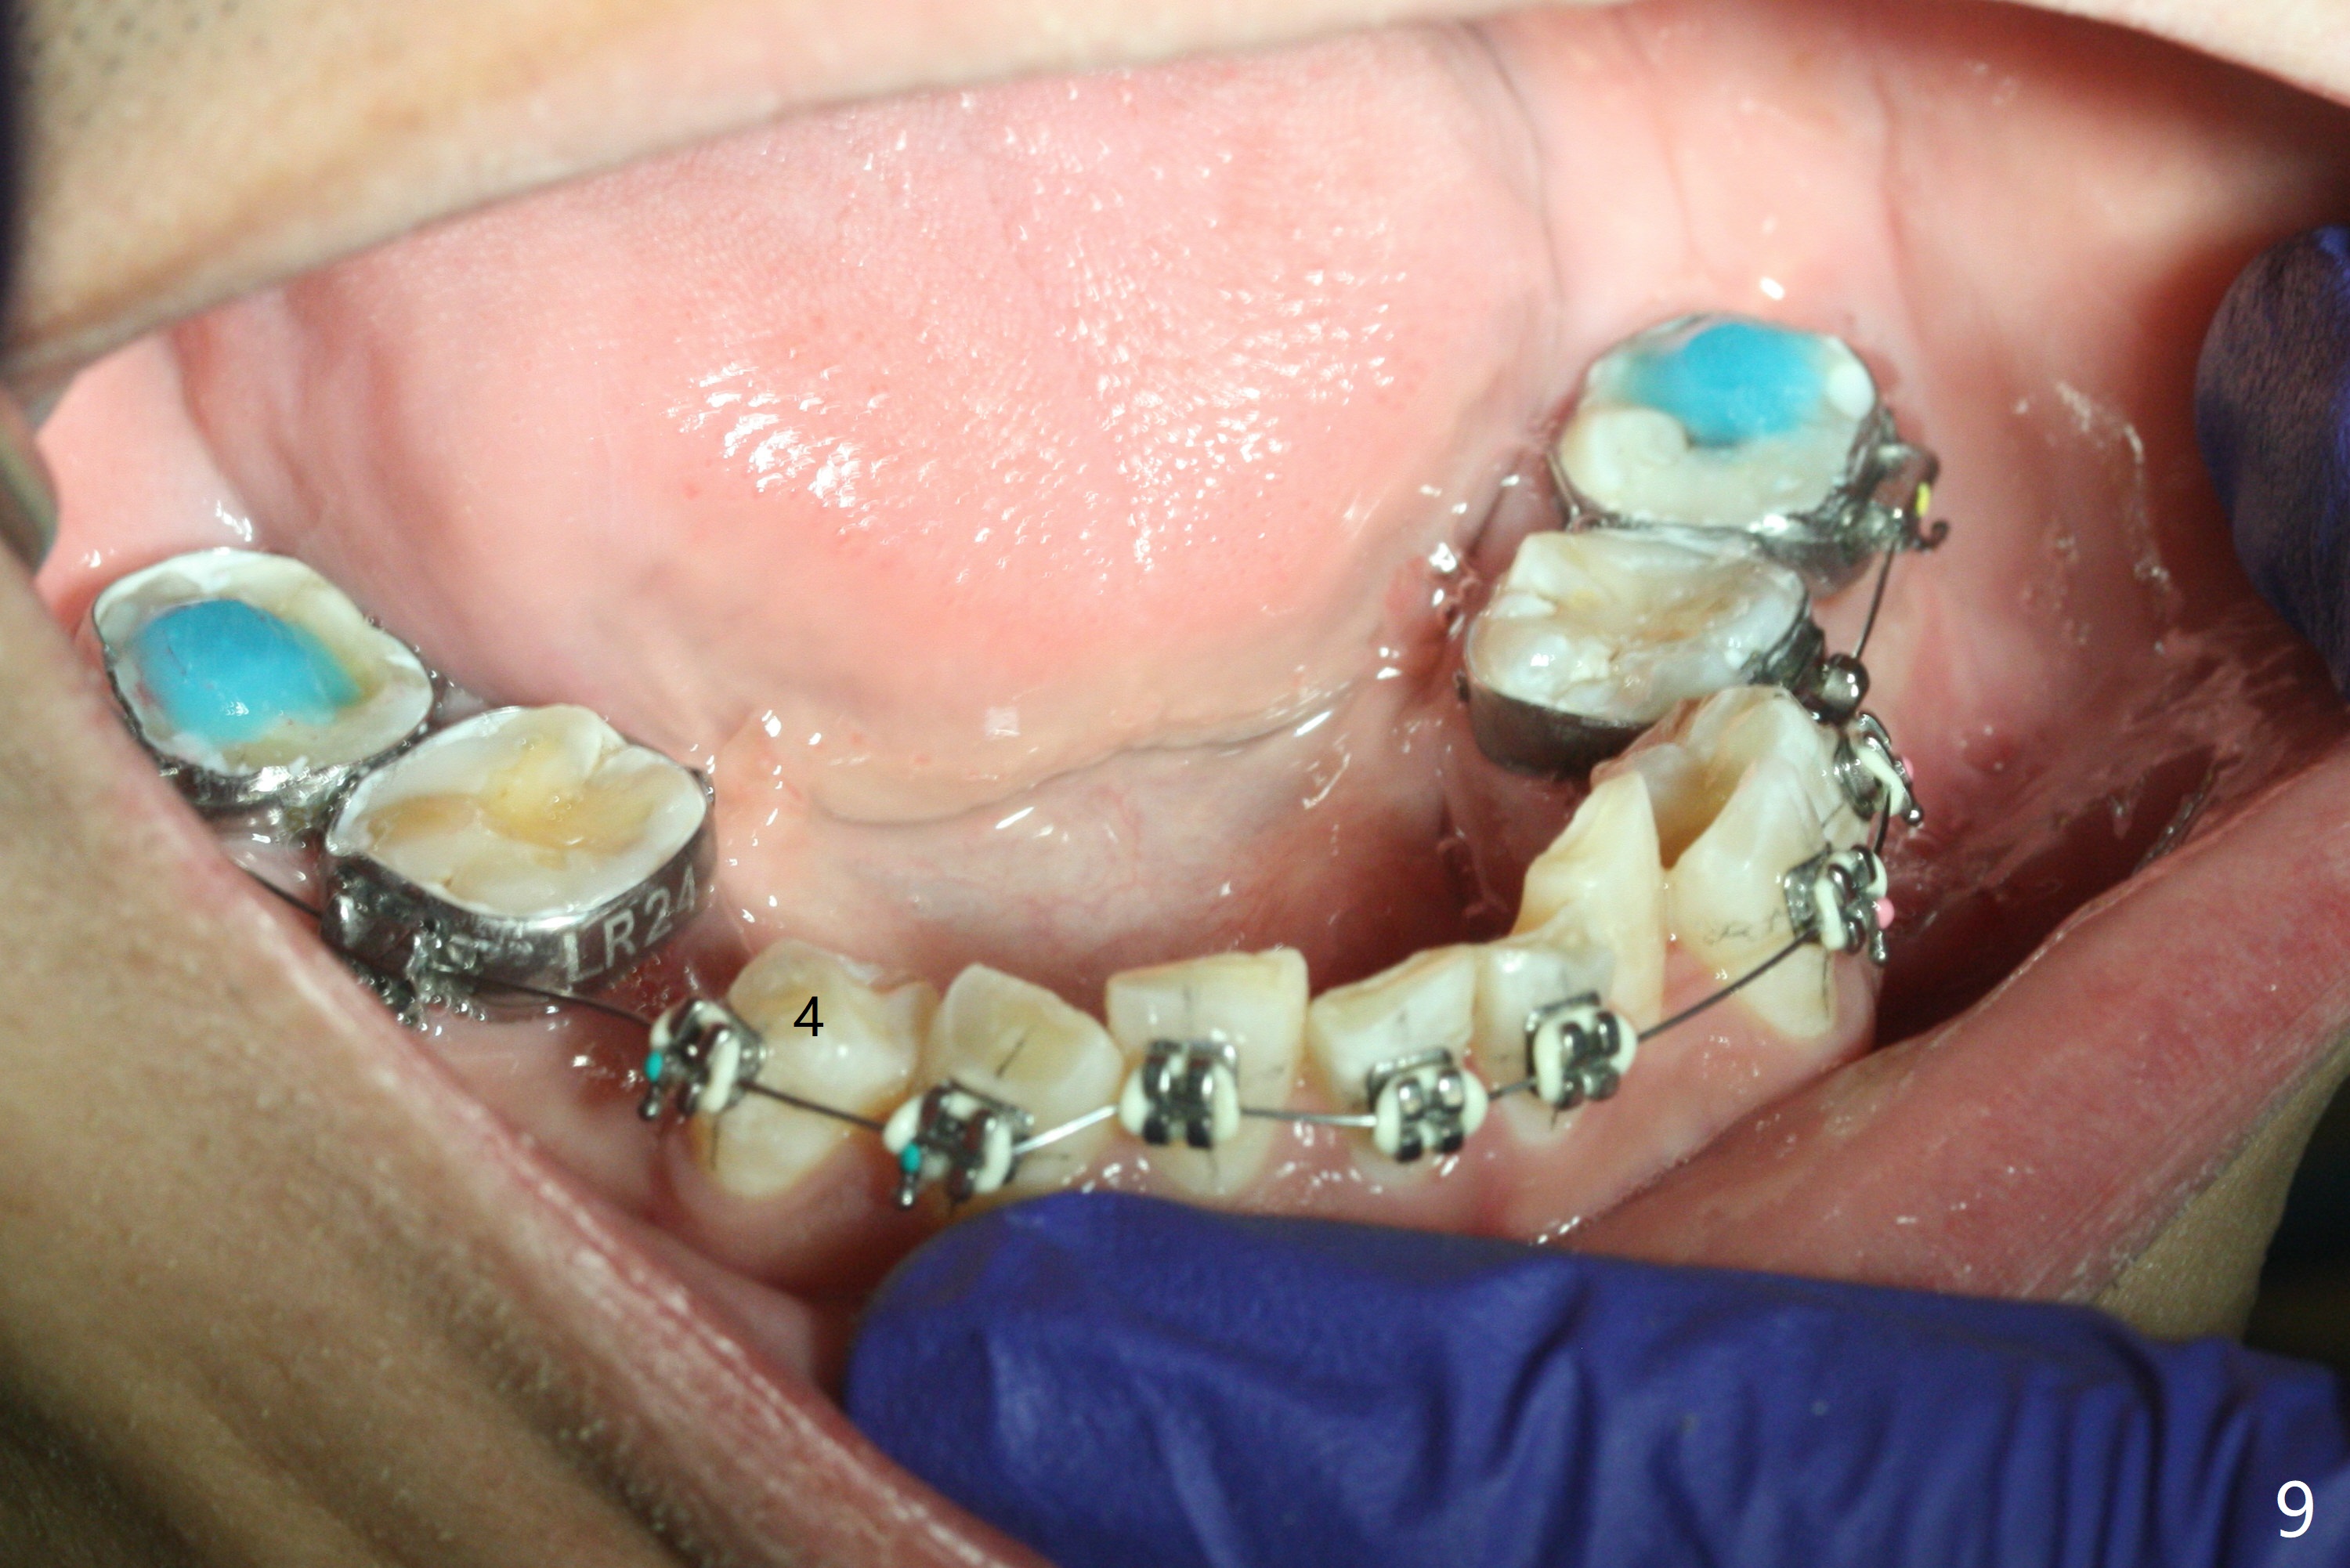

Severe crowding (Fig.1-7) appears to be alleviated especially 2 months after UR5 extraction. Diastemata seem to form mesial and distal to UR2 (Fig.8). Because of severe wear at UR3 (Fig.6), there is no bracket placement differential around it (Fig.8 (14 niti wire)). Lower bands and brackets are placed a week later (Fig.9-11). Because of tight space between LR4 and the opposing tooth (Fig.10), band adhesive is applied to L7 occlusal surface to open the bite (Fig.9). There is an abrupt kink of 12 niti wire between LL4 and 6 (Fig.11). The latter does not improve much in a month; the wires remain the same (Fig.12). For LL2, LR4 has been retracted for ~ 1 month (Fig.13). There is mild tension when 18 ss wire is inserted between LL4 and 6 five point five months post banding (Fig.14). UR4 has been distalized for a month using buccal power chains x3 resulting in rotation; to counter the rotation, a lingual button is placed with power chain x3 lingual and x2 buccal (Fig.15). With space gaining, it is time to finish definitive filling (Fig.16 *). Next visit check midlines, overjet, interdigitation, and molar classification. R4s distalize, but associate with rotation because of power chains buccal and lingual 8 months post banding (Fig.17,18). With the use of the same wires, power chains are applied lingual to continue distalization and rotation correction (Fig.20,21). Lingual buttons are placed at L2s buccalization (Fig.19) and mesialization (Fig.22,23). It appears that space should be created distal to LR3. That is that the lower anterior teeth should be shifted to the right, although it may be not appropriate for the midline.